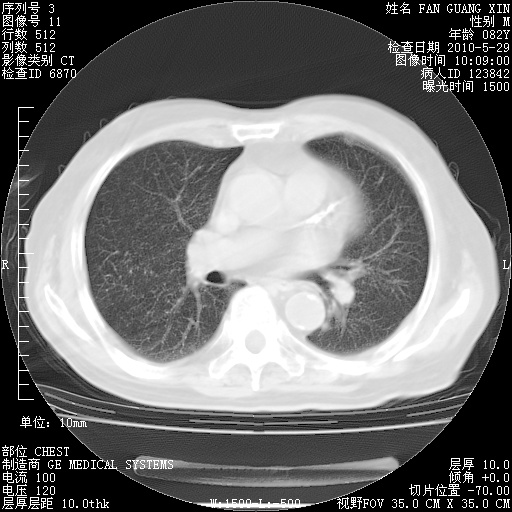

再治疗10天后的肺部CT

阅读此次胸部CT,肺间质渗出性改变较入院时有吸收。目前从体温、白细胞、中性分叶明显增高,肯定存在细菌感染(发生医院感染哦,若无消化道及泌尿系统等感染的依据,肺部感染可能大)。若你院头孢哌酮舒巴坦钠耐药率较高,同意你的方案,若48小时体温仍高,可考虑使用碳青霉稀类抗菌药物,同时可予超声雾化、注意滴数时加大液体量。白蛋白33.30g/L较低哦,需加强营养等支持治疗。